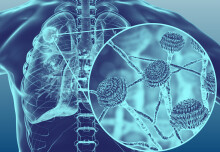

Mpox insights

Mpox: WHO experts respond to questions on current outbreak

The WHO has declared current Mpox outbreaks are of 'International Concern', but how does the situation differ from previous public health emergencies?